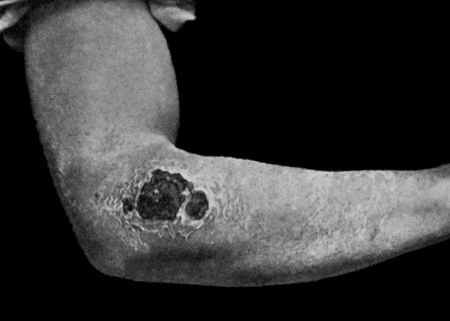

28.Malignant Pustule third day after infection 122

29.Malignant Pustule fourteen days after infection 122